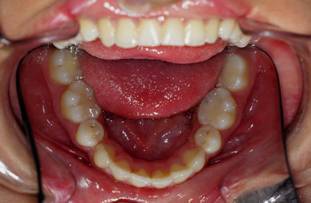

Je crois cette fois ca va marcher. Il s'agit d'une jeune fille de 12 ans, origine franco-libanaise, deja reglee depuis qqs mois. Classe II1 dentaire. Une demande majeure pour la patiente et sa maman: Les dents du haut sont trop en avant, il ne faut surtout pas les avancer ou les garder comme ca!!!

1 aswyzj - Eugenol

2 yzorem - Eugenol

3 uk1wzr - Eugenol

4 nsnllc - Eugenol